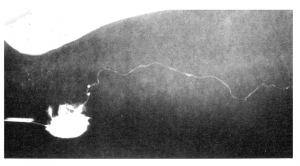

The excessive amount of fatty tissue present in lipedema compresses the lymph collectors of the superficial lymphatic system, which are embedded in the fatty subcutaneous tissue. Lymphangiographic imaging shows that the lymph collectors within the proliferated fatty tissue have a coiled or corkscrew-like appearance rather than passing fairly straight towards the lymph nodes as is the case in healthy tissue. This can result in a reduced transport capacity of the lymphatic system in the affected area.